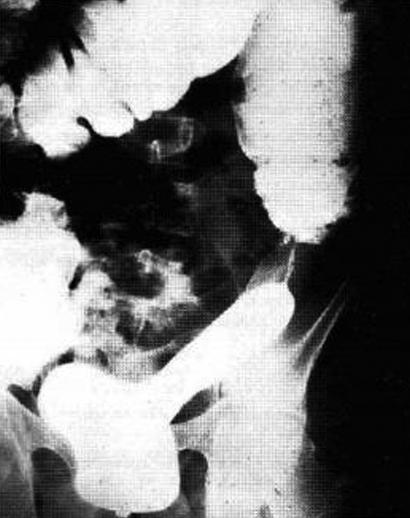

Image

radiologiqe ASP du maladie de Crohn est image de

epaissisement de la paroi du colon avec image empreindre de pouce .

Image radiologique ASP du maladie de

Crohn est image d'epaissisement de la paroi du colon

avec images de empreintes de pouce . Cliche ASP de

face |